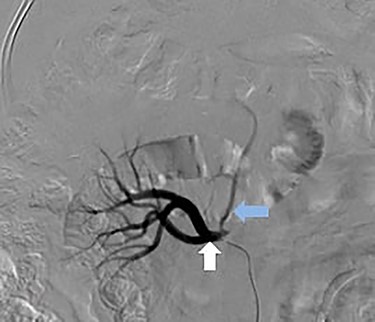

Selective catheter angiogram of right renal artery (white arrow) showing a branch near its origin (blue arrow) supplying the hepatic lesion.

Superselective delayed phase angiogram of right renal artery using microcatheter showing well-defined tumor blush.